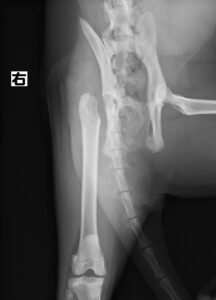

【整形外科】 右大腿骨頭すべり症

ジャンプした拍子に右後肢跛行とのことでかかりつけ医を受診後、セカンドオピニオンとして当院の整形外科に来院されました。若い雄猫に多く見られる「大腿骨頭すべり症」と診断。ご家族様と相談の上、骨頭切除を実施しました。経過は順調でしたが、その6ヶ月後に逆側も同様に骨折し、同治療を行いました。結果的に両側の骨頭切除が行われましたが、経過は良好です。